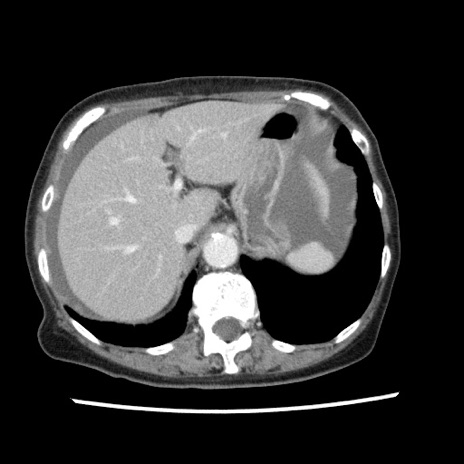

冠状断像

【症例】80歳代女性

【主訴】腹痛

【現病歴】8時間前から腹痛あり来院。

【既往歴】糖尿病、脂質異常症、子宮体癌にて子宮全摘術

【身体所見】意識清明・会話良好だが腹痛で苦悶様、全腹部にわたって反跳痛と圧痛あり

【データ】WBC 13600、CRP 0.14、LDH 224、CK 90